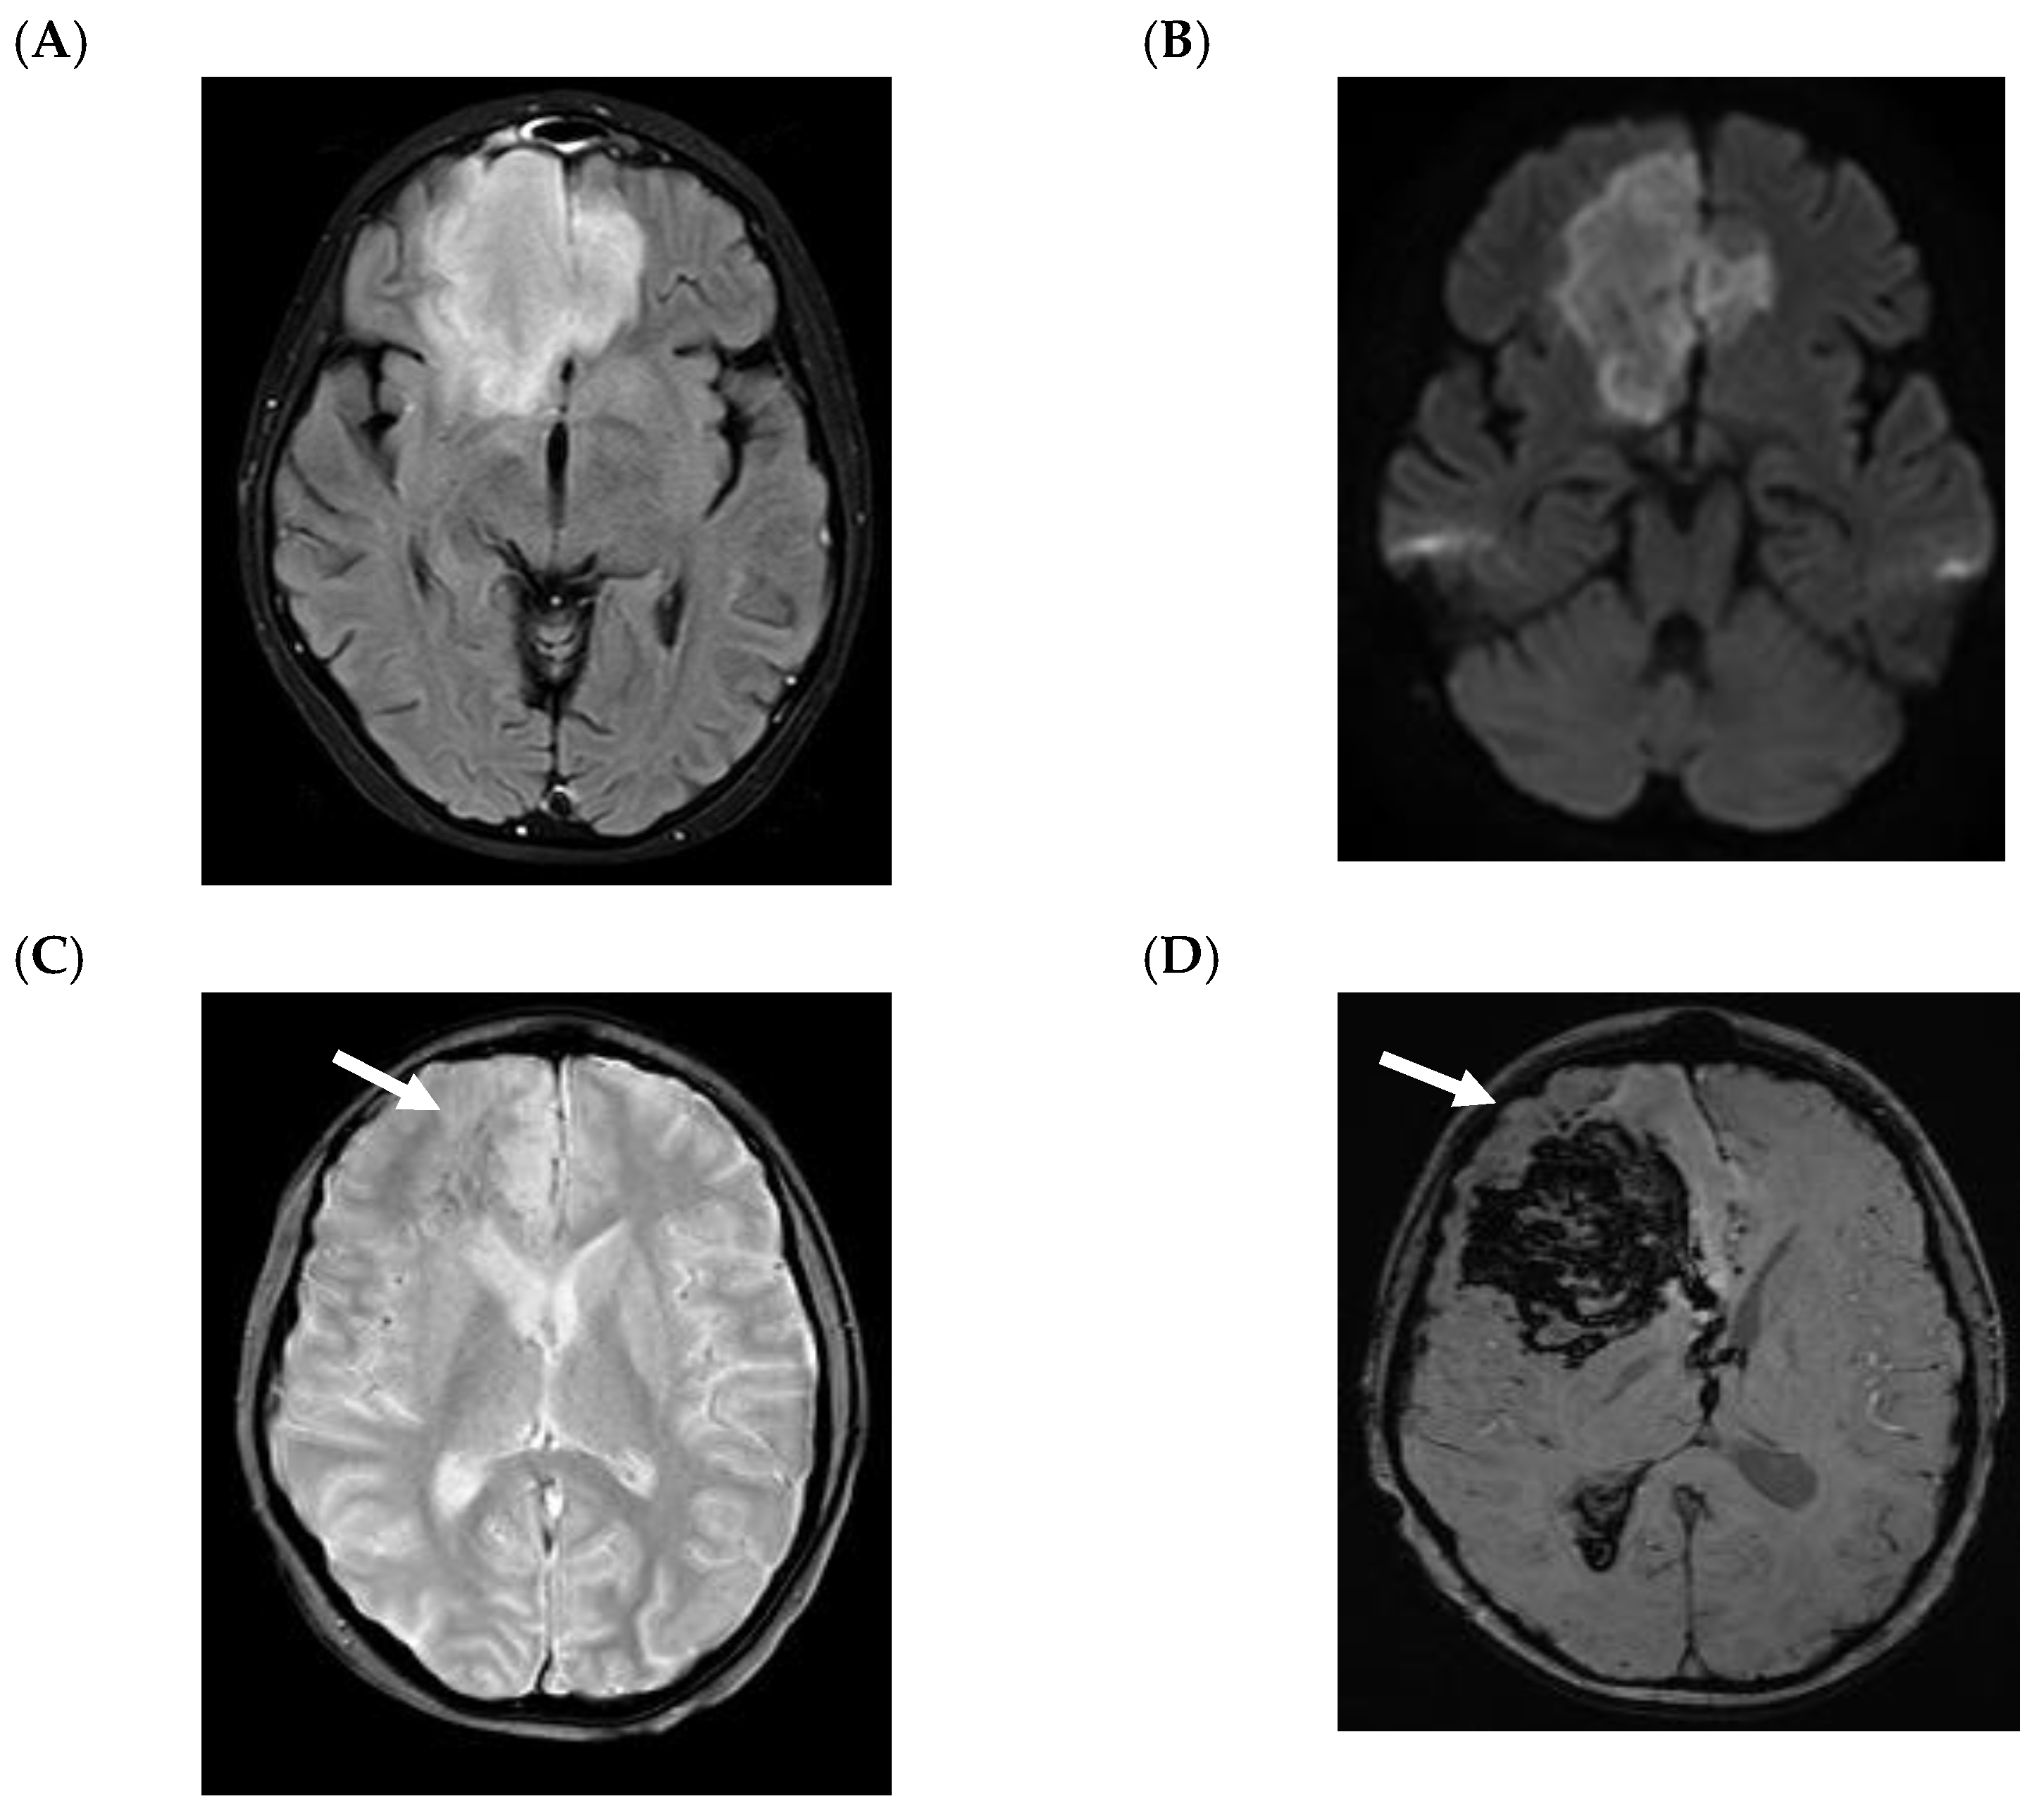

5.2. CNS Manifestations

- Antulov, R.; Dolic, K.; Fruehwald-Pallamar, J.; Miletic, D.; Thurnher, M.M. Differentiation of pyogenic and fungal brain abscesses with susceptibility-weighted MR sequences. Neuroradiology 2014, 56, 937–945. [Google Scholar] [CrossRef]

- Mathur, M.; Johnson, C.E.; Sze, G. Fungal infections of the central nervous system. Neuroimaging Clin. N. Am. 2012, 22, 609–632. [Google Scholar] [CrossRef]

- Britt, R.H.; Enzmann, D.R.; Placone, R.C., Jr.; Obana, W.G.; Yeager, A.S. Experimental anaerobic brain abscess. Computerized tomographic and neuropathological correlations. J. Neurosurg. 1984, 60, 1148–1159. [Google Scholar] [CrossRef] [PubMed]